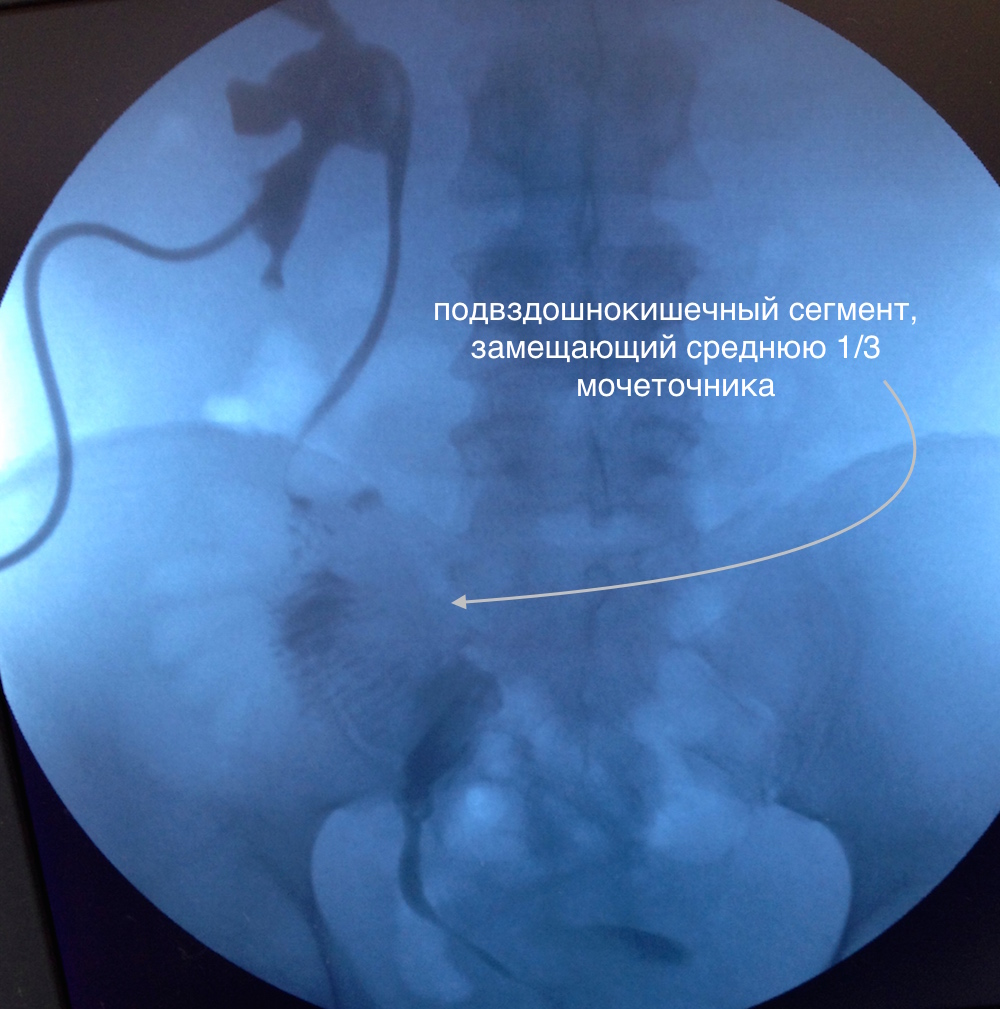

Тонкокишечная пластика резецированного сегмента мочеточника